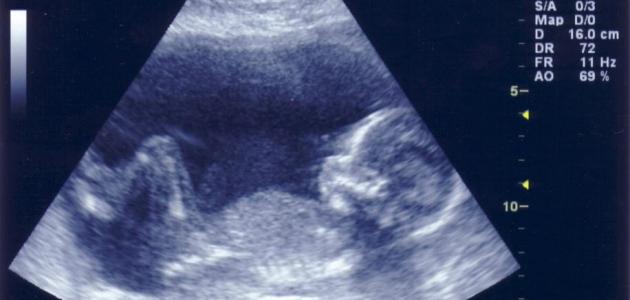

- أضمن طريقة لمعرفة نوع الجنين بدقّة هي فحص الأيكو أو السونار عند الطبيب، وهو عبارة عن موجات صوتية يُصدرها جهاز السونار تدخل هذه الموجات داخل بطن المرأه و وعند الاصطدام بجسم ما ترتدّ هذه الموجات، وهذه الموجات لا تكون ضارّة سواء بالجنين أو المرأة الحامل، وعندها يستطيع الطبيب رؤية الجنين ومعرفة قياساته وحجمه وتستطيع الموجات أن تعرف وتحدّد الأعضاء التناسلية لهذا الجنين وبالتالي معرفة إذا كان ذكراً أم انثى.